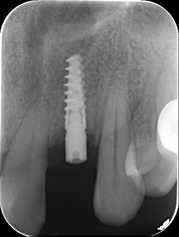

术后即刻CBCT

术后CBCT

术前术后CBCT对比

唇侧过量植骨希望最终能够实现存量骨组织>2mm。

术后4.5个月根尖片

ISQ动度值颊舌/近远中为70/73。

戴牙后20天复查X线检查